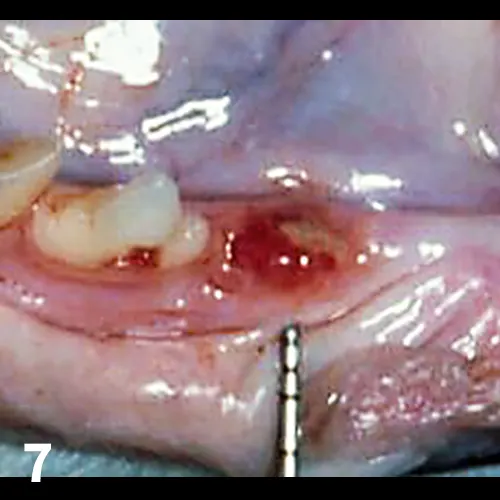

Tooth resorption is a form of external resorption. Resorption is the loss of hard tissues caused by cells called odontoclasts; external resorptions starts in the root’s cementum layer and can extend into the dentin. Previously called cervical neck lesions, feline caries, and feline odontoclastic resorptive lesions (FORLs), tooth resorption affects 25% to 75% of the cat population over age 2.11  The odontoclasts, which are derived from hematopoietic stem cells, migrate from the blood cells of the periodontal ligament space toward the external root surface and start destroying the dental hard tissue.11 (See Figures 5-7.)

FIGURE 5

Tooth resorption: Note the granulation tissue growing into the enamel defect (arrow)